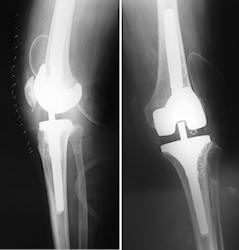

Kollateral rekonstrüksiyonu için yukarıda sayılan ön şartlar sağlanmıyorsa seçkin tedavi revizyon diz protezidir. Revizyon sırasında varus-valgus düzleminde yumuşak doku dengesi sağlanır, fleksiyon ve ekstansiyon aralığı eşitlenir ve sıklıkla posterior stabilize veya varus-valgus kısıtlı bir implant kullanılır. Sıklıkla stem extension gerekli olur. Buna rağmen stabilite sağlanamazsa menteşe tipi protezler kurtarıcı cerrahi olarak gündeme gelir.Flekisyon ekstansiyon aralığı dengesizliğine bağlı instabilite

Gevşek fleksiyon aralığının tedavisi revizyon diz protezidir. Yumuşak doku dengesinin sağlandığı, fleksiyon-ekstansiyon aralığının eşitlendiği, arka çapraz bağı kesen implantlar ile revizyon yapılmalı, hala stabilite sağlanamıyor ise menteşe tipi protezler ile revizyon yapılmalıdır (McAuley JP:J Arthroplasty 2003 18(3 Suppl 1):51-4 ).

Revizyon sırasında kemik stoğu iyi, eklem çizgisi kabul edilebilir, ilk insert ince (nadir) ise, primer implantlar ile revizyon yapılabilir. Bu sırada distal femoral rezeksiyon yapılarak daha kalın insert yerleştirilir ve PS tasarımlı bir protez kullanılır. Daha sık olarak ise primer implantlarla revizyon mümkün değildir. Bu durumda, daha büyük femoral komponent off-set stem ile posteriora alınarak yerleştirilir. Posterior femoral augment kullanılır. Bu sırada patello-femoral kompartmanın aşırı doldurulmamasına özen gösterilmelidir.

Menteşe tipi protezler

İkinci jenerasyon rotasyonlu menteşe tipi protezlerde erken gevşeme sorunları bir miktar da olsa azaltıldı. Günümüzde çimentosuz modüler, diyafizi dolduran stemlerin kullanımı, daha iyi menteşe yapısı ve daha iyi patello-femoral eklem tasarımı sayesinde daha iyi klinik sonuçlar bildirilmektedir.

Barrack, 22 dizin, 55 aylık izleminde hiç gevşeme ve patello-femoral sorunla karşılaşmadığını bildirmiştir (Barrack RL:Clin Orthop 2001, 392:292). Springer ise 26 dizin, 58 ay izleminde, 5 enfeksiyon, 2 gevşeme rapor etmiştir (Springer BD: Clin Orthop 2004, 421:181-7). Buna rağmen, menteşe tipi diz protezlerinin uzun dönem sağkalım oranları, kısıtlı olmayan protezlere göre daha kısa olduğu için yaşlı ve sedenter hastalarda tercih edilmelidir.